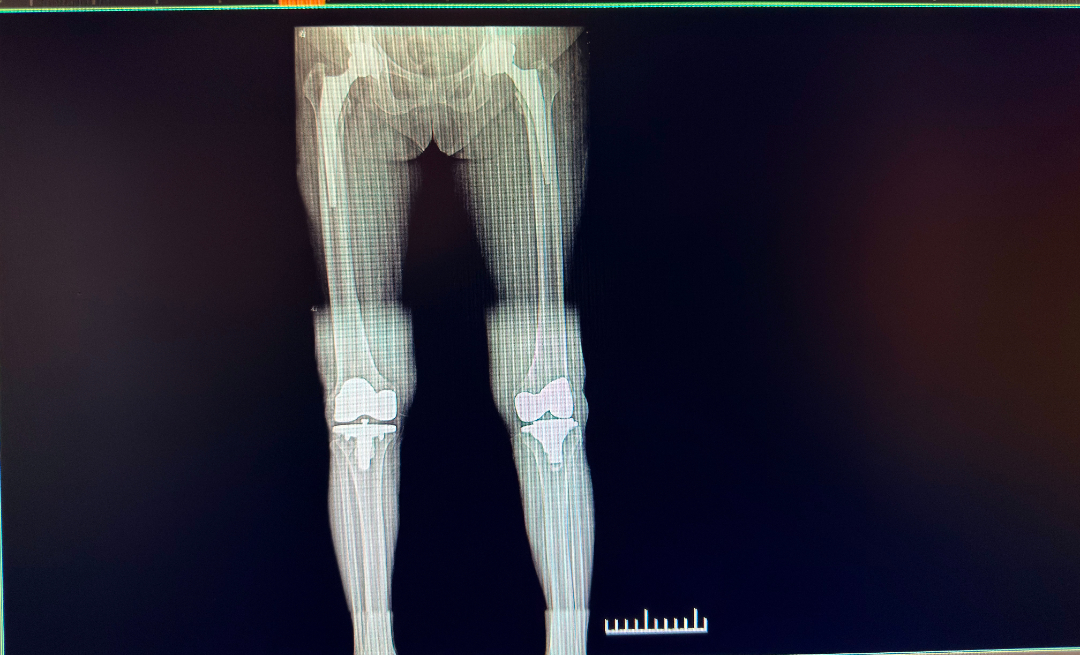

近日,在我院骨伤关节创伤科,一位高龄患者的治疗历程生动诠释了“信任”与“技术”的双向奔赴。该患者因双侧膝关节及双侧髋关节病变,先后4次选择周武忠主任团队实施手术,从双膝关节置换到双髋关节置换手术,每一次治疗均取得显著疗效,最终实现行走自如、生活质量全面提升。这不仅展现了科室在骨伤与关节等领域的综合实力,更凸显了患者对团队技术和护理服务的高度信赖。

时隔2年后,老人再次找到周主任,由于长期的关节炎导致的膝盖红肿胀痛让老人生活苦不堪言,周主任检查后发现右膝关节尤其严重,活动度仅剩60°,软骨严重磨损,骨质增生明显。保守治疗已经不能起到作用,只能通过关节置换才能重新恢复关节功能,经过周密的术前准备,周主任带领科室团队为老人进行了“右膝关节置换术”,手术非常成功,右膝关节疼痛明显缓解。几年后,左侧膝关节也发生了不可逆的病变,老人又找到周主任,并成功完成左膝关节置换术。术后康复一段时间后,老人摆脱疼痛困扰,轻松地完成日常生活中的各种活动,如正常走路、上下楼梯、跑步、跳舞等日常活动。

右髋关节置换—右膝关节置换—左膝关节置换—左髋关节置换,1份信任,4次手术,背后是周武忠主任团队精湛的医疗技术和团队优质的护理服务。科室始终坚持"以患者为中心"的服务理念,在提供专业治疗的同时,更注重人文关怀,为患者点燃希望,也书写着一个个充满温情的康复故事。